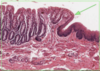

What type of epithelium is this?

Describe?

Intestinal epithelium

- Enterocytes with goblet cells

- Epithelia sit on BM permeability barrier between epithelium and connective tissue

- Microvilli at the apical surface (brush border)

- Brush border increases surface area

- Small intestine = simple columnar

Larger intestine > goblet cells

What is this a slide of?

What stain has been used?

Microvilli/intestinal

Stained with PAS and haematoxylin

- Microvilli with carbohydrate rich glcocaylx

- Goblet cells and basement membrane rich in hexose

- The stain is magenta